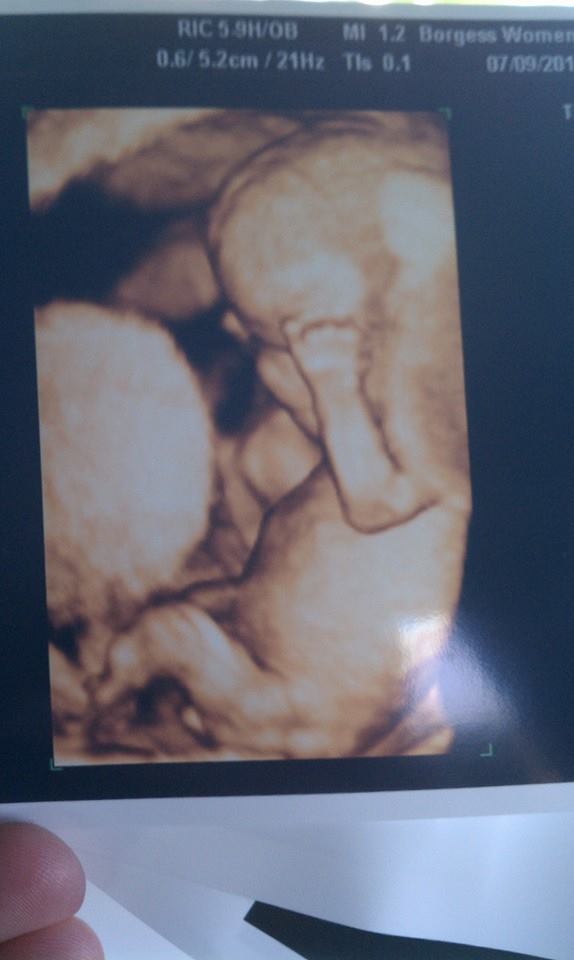

• At my dr's office it's just a flip of a switch on the keyboard.  I just had an ultrasound last week for 12 weeks (cerclage stitch next week. that was the need for the u/s).  She pushed a button and there was our baby in 3d.  I loved it.  Made it more real than the regular pics.  Here's ours.

Our pics still look pretty blurry because my little guy is breech which doesnt give you the best views.

Even though it is a little creepy, I still think its cool.  Its my son in there,  I cant see him 100% how hes going to look when he arrives in Sept, but you can still make out a lot of his features which makes it cool for me.

• i could not wait to see my baby's face! Now i love just staring at her !!! she likes to have her hands in her face though and we got video of her so i watch that alot hehe i feel like it made her more Real to both my husband and I, So in love with our baby girl!!

• They do look super creepy at 20 weeks, but my friend just got one at 33 weeks and she was so cute and chubby! If I get one, I will definitely wait until at least 32 weeks so she looks more like a baby. Now at 21 weeks, she is too skinny and would definitely look creepy.